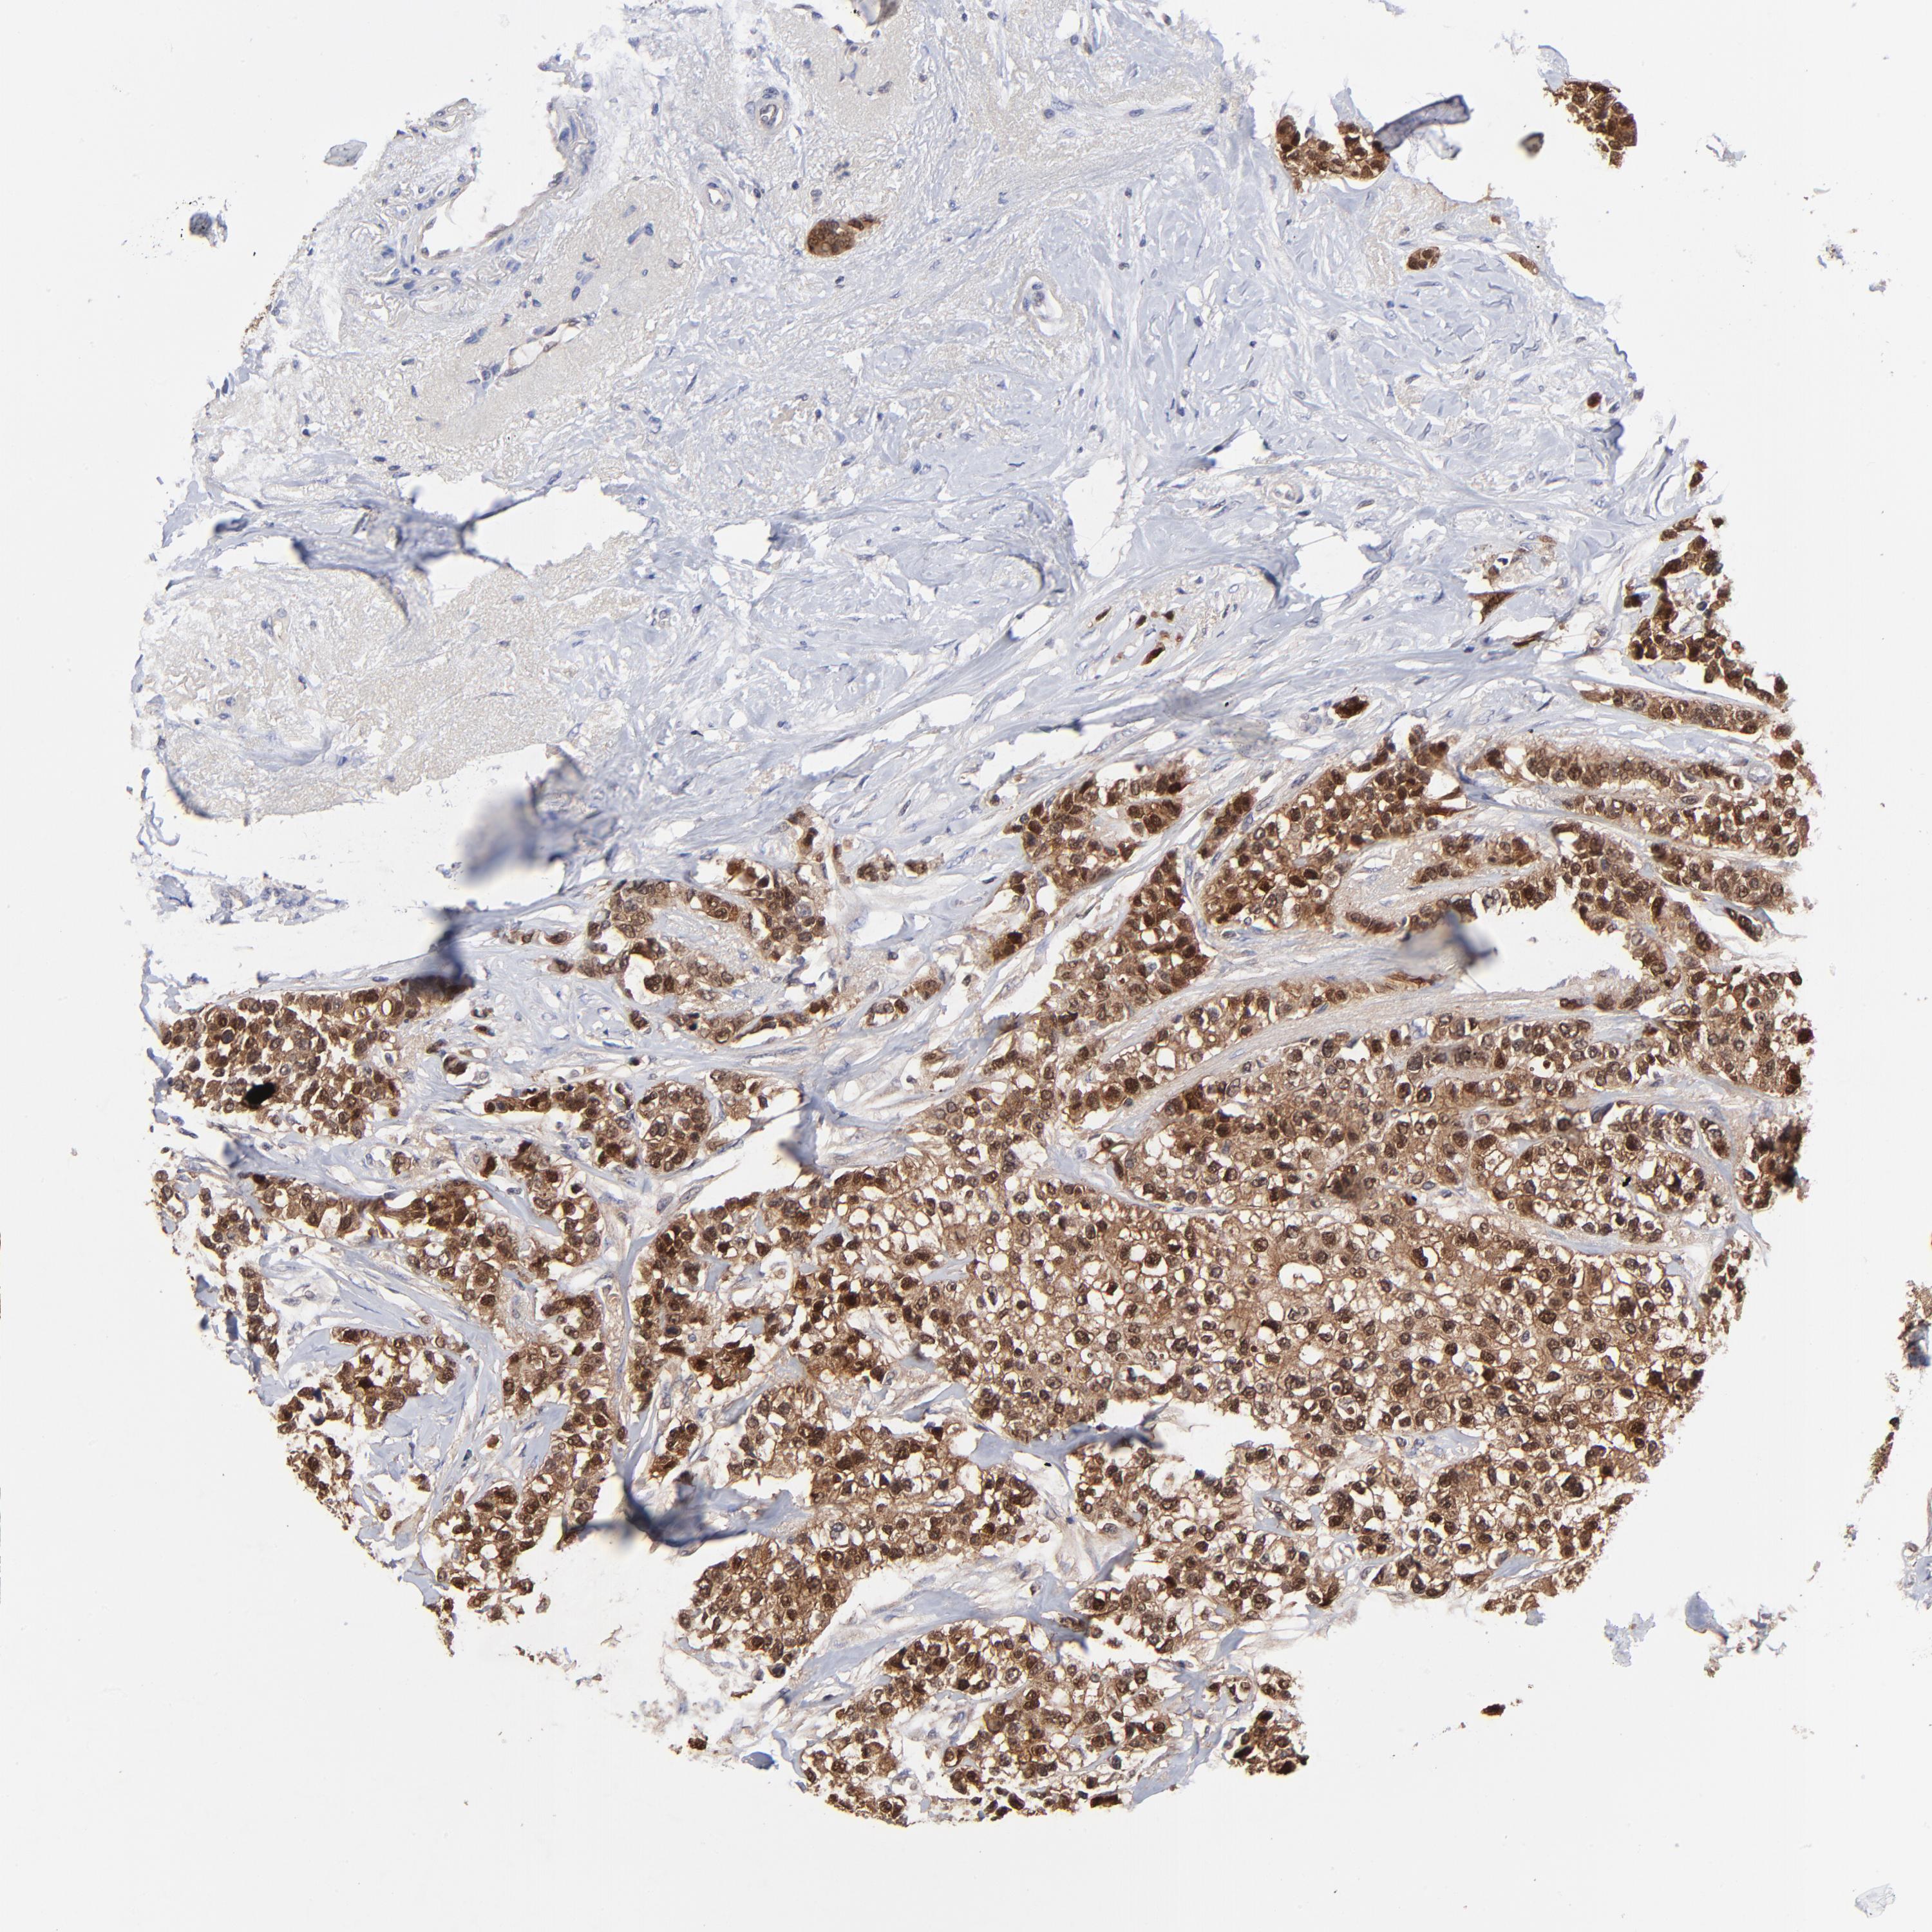

BRCA TCGA BRCA VALIDATION PROTEIN EXPRESSION

ANTIBODIES

AND

VALIDATION